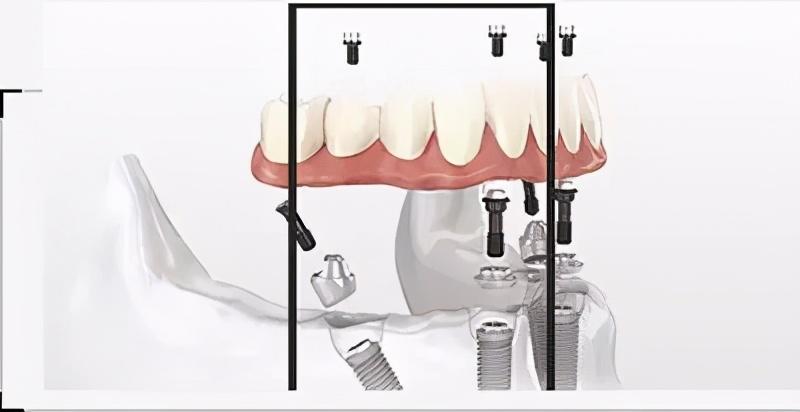

注明:此植體只是模擬位置,不做確切種植位置。